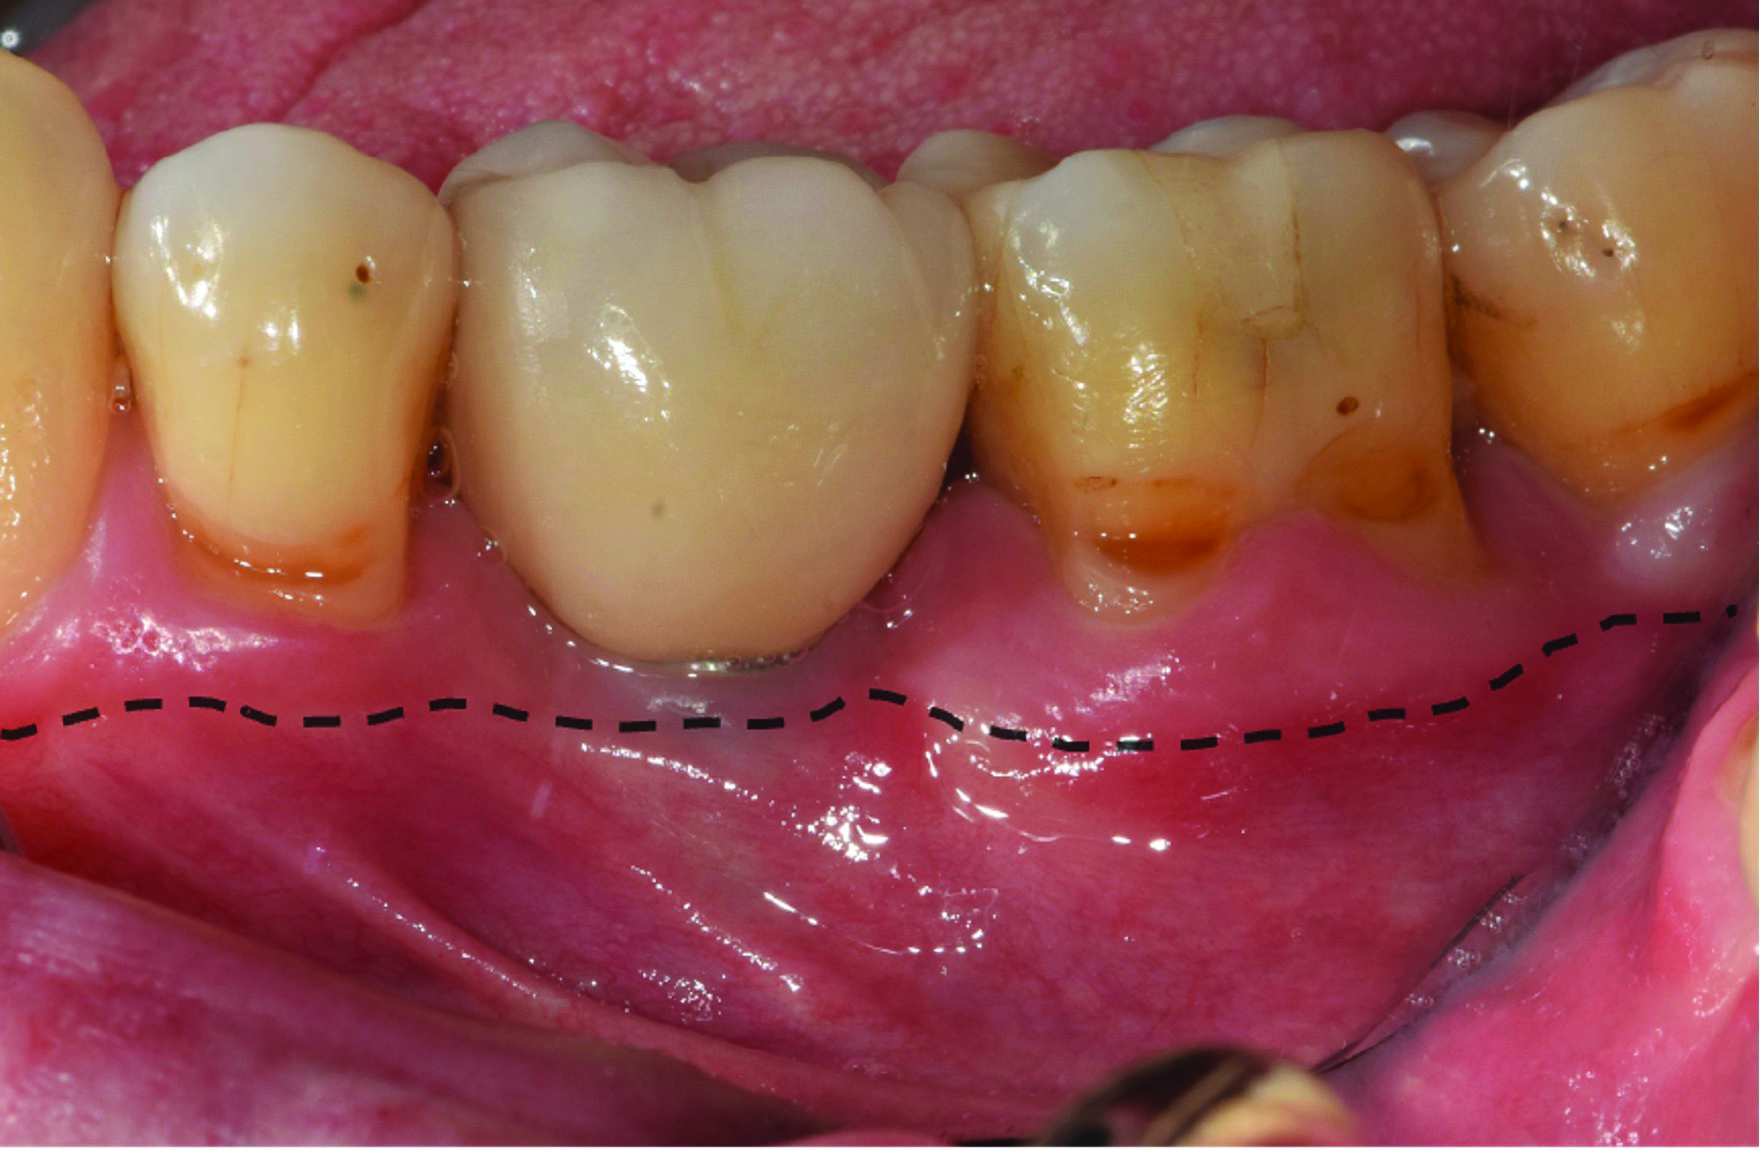

A deficient dimension of keratinized mucosa width (KMW) around dental implants is often related to patient discomfort during oral hygiene (Figure 1). Literature suggests the dimension of KMW should be considered as a risk factor for peri-implant mucositis and peri-implantitis.1-4 KMW is also associated with patient satisfaction regarding implant esthetics. Mucosal thickness (MT) is crucial for both esthetic outcomes and peri-implant health.5-7 Thicker mucosal tissue provides stability for the mucosal margin, which leads to less risk of mucosal recession. This underscores the importance of considering tissue thickness in implant planning and restoration.

KMW is the dimension of keratinized soft tissue extending from the mucosal margin to the mucogingival junction (MGJ) in the apicocoronal direction. KMW is the coronal component of the peri-implant soft tissues, and beyond these tissues apically is the non-keratinized alveolar mucosa (Figure 1 through Figure 3). Where KMW is absent in certain conditions, there is solely non-keratinized peri-implant mucosa adaptation to the implant prosthesis. KMW is measured clinically with an instrument such as a periodontal probe in the apicocoronal direction, or an estimate of KMW can be made based on photographs. While as a clinical guideline or for research purposes it has been proposed that at least 2 mm of KMW be present, this amount is still debated as to whether or not it is necessary.8

MT is the horizontal dimension of the peri-implant soft tissue and may or may not be keratinized. MT is an important aspect of implant esthetic outcomes, especially at the most coronal aspect around the implant restoration. Around thin mucosa the color of the underlying restoration material may show through and result in esthetic deficiencies (Figure 1). Conversely, thick tissue can minimize the shading effect of underlying restoration materials and may compensate for any bony dehiscence around the implant body. In a systematic review, it was reported that after soft-tissue augmentation was conducted to increase MT, less interproximal marginal bone loss resulted around the implant.9

Fig 1. The peri-implant mucosa of implant No. 19 presents erythema with a lack of KMW. The dark color of the underlying restoration is showing through the thin peri-implant mucosa. The dotted line indicates the MGJ. The distance from the margin of the peri-implant mucosa to the MGJ is the KMW.